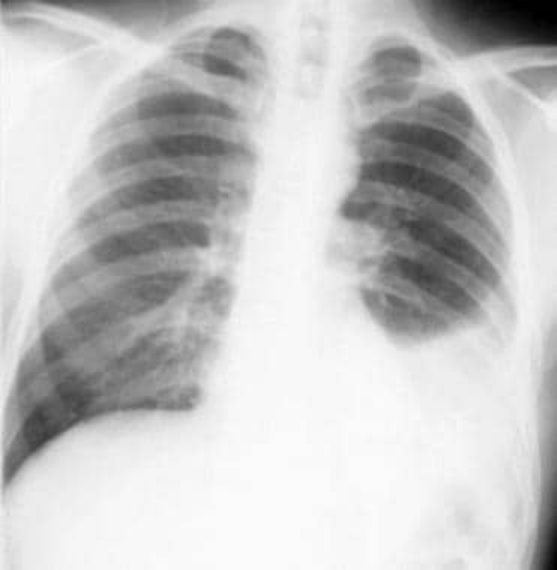

非小细胞肺癌。支气管镜检查。大的中央病变被诊断为非小细胞癌。